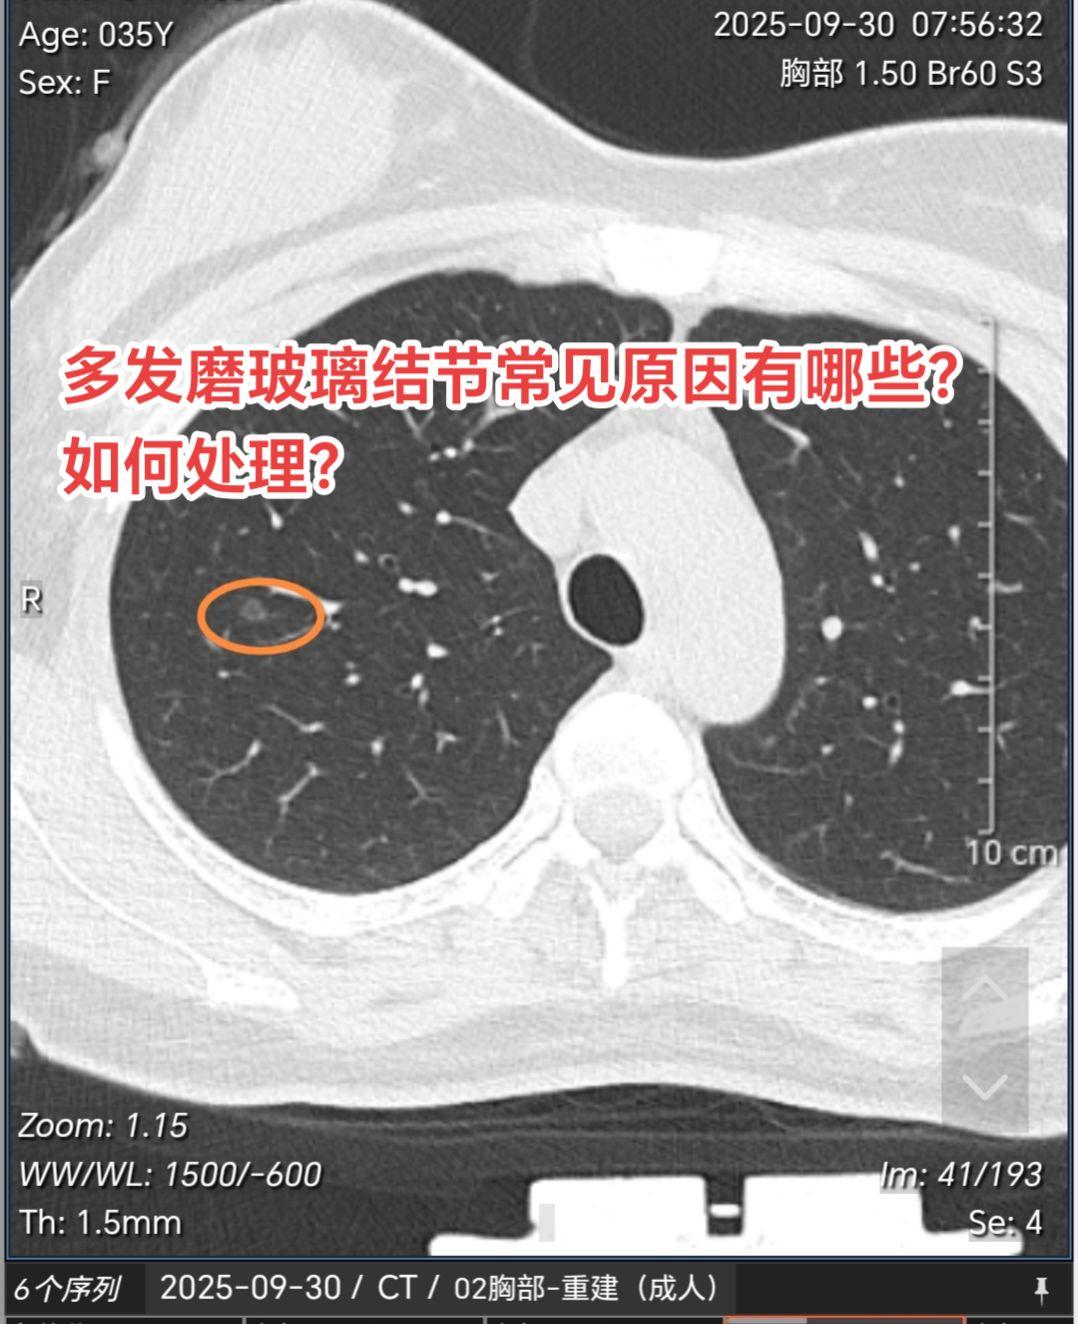

多发磨玻璃结节常见原因有哪些?如何处理?这种多发磨玻璃结节如果经半年左...